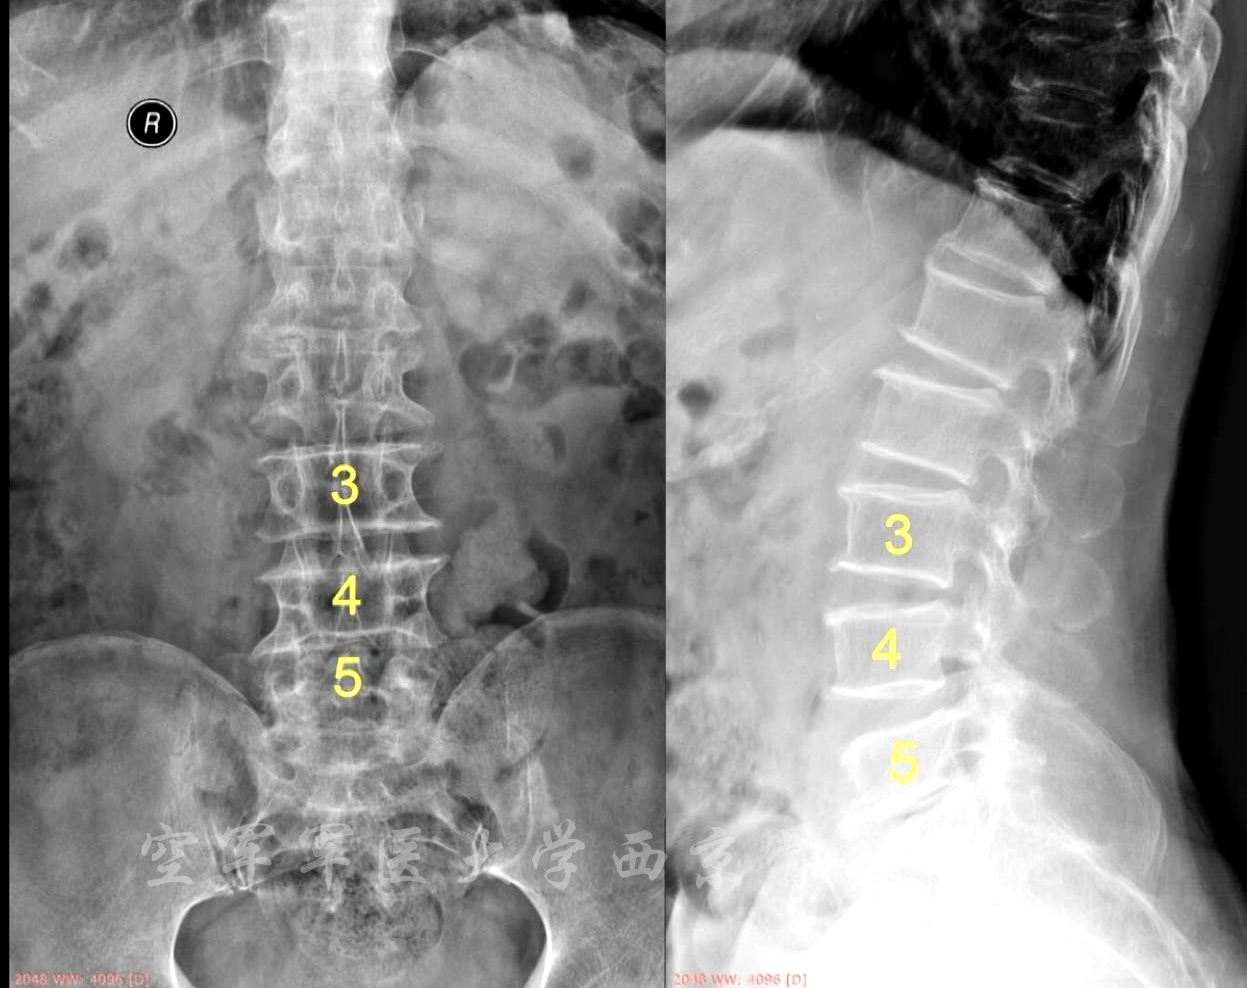

术前X线正侧位片

术前MRI

术前CT